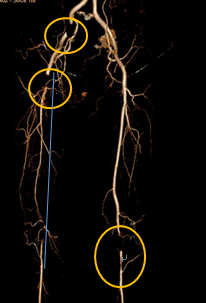

▲ 双下肢动脉多发闭塞

王兵教授一听症状,就让老先生脱掉鞋子,右脚发紫,左脚有点苍白,不是正常的红润,脚趾甲跟灰指甲一样失去正常的光泽。一摸温度,右脚明显比左脚低,而且双脚的足背动脉搏动都消失了。于是给病人做了个下肢动脉的CTA,结果CTA回示双腿的动脉血管多发硬化闭塞。

王兵教授及崔文军主任进行科室讨论给病人制定了“杂交手术”治疗方案,经右侧股动脉切开取栓,然后同时处理双侧病变,手术取出一部分血栓,放置了2枚支架,成功将两条腿的血管成功打通。手术后,经过护理后,顺利出院,走路基本恢复正常。